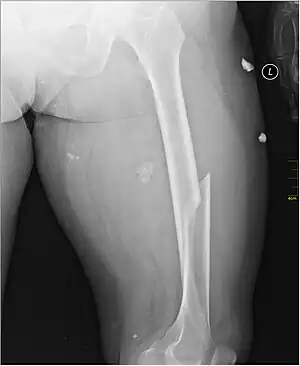

| X-ray image of a femoral shaft fracture | |